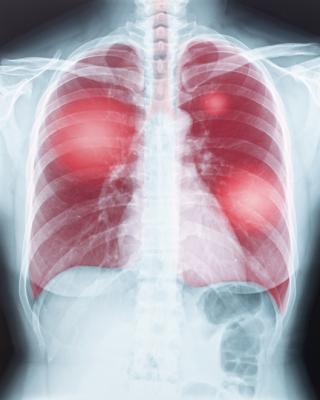

July 30, 2020 — A World Health Organization (WHO) rapid advice guide on the use of chest imaging in the diagnosis and management of COVID-19 was published in the journal Radiology.

The rapid guide includes three diagnosis recommendations and four management recommendations covering patients with suspected or confirmed COVID-19 with different levels of disease severity, throughout the care pathway from outpatient facility or hospital entry to home discharge. It also offers considerations about implementation, monitoring and evaluation and identifies research needs.

The purpose of the guide is to support WHO Member States in their response to the COVID-19 pandemic by providing up-to-date guidance on use of chest imaging in adult patients with suspected or confirmed COVID-19, including chest radiography, computed tomography and lung ultrasound. It covers the care pathway from outpatient facility or hospital entry to home discharge. The guidance is provided for patients with different levels of disease severity, from asymptomatic individuals to critically ill patients.